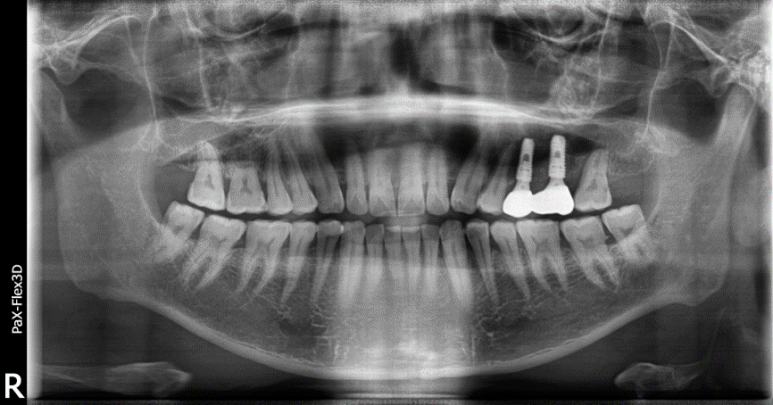

| 심각한 염증으로 발치후 임플란트 한 치료 사례 |

49세 남성

(전) 2021-12-28, (후) 2022-08-06

상기 환자분도 위 어금니 통증이 너무 심해서 내원하신 분으로, 파노라마 촬영상 치아 뿌리 끝에 심각한 염증이 관찰되었습니다.

또한 염증으로 인해 치아가 흔들리고 있던 상황이었기 때문에 발치 후 임플란트 시술을 고려할 수밖에 없었는데요.

특히 심한 염증으로 인한 치근낭(치아뿌리 끝에 물혹이 생긴 질환)이 관찰되어, 발치하면서 치근낭적출술도 함께 시행하였습니다.

치근낭은 대부분 증상이 없지만 낭종이 커지면서 부종이 생길 수 있고, 잇몸뼈가 녹아 치아가 흔들리게 할 수 있습니다.

그래서 환자분 케이스는 발치 후 즉시 식립이 어려워서 당일 뼈이식만 진행하고, 3개월 후 지연 식립을 진행하게 되었습니다.

염증이 워낙 심했던 케이스라 최종 보철물을 올리기까지 약 8개월 정도가 소요되었는데요.

이처럼 심각한 염증은 발치후 임플란트 기간을 지연시킬 수 있습니다. 그러니 미리미리 치과에 내원하셔서 정기검진받으시길 바랍니다.